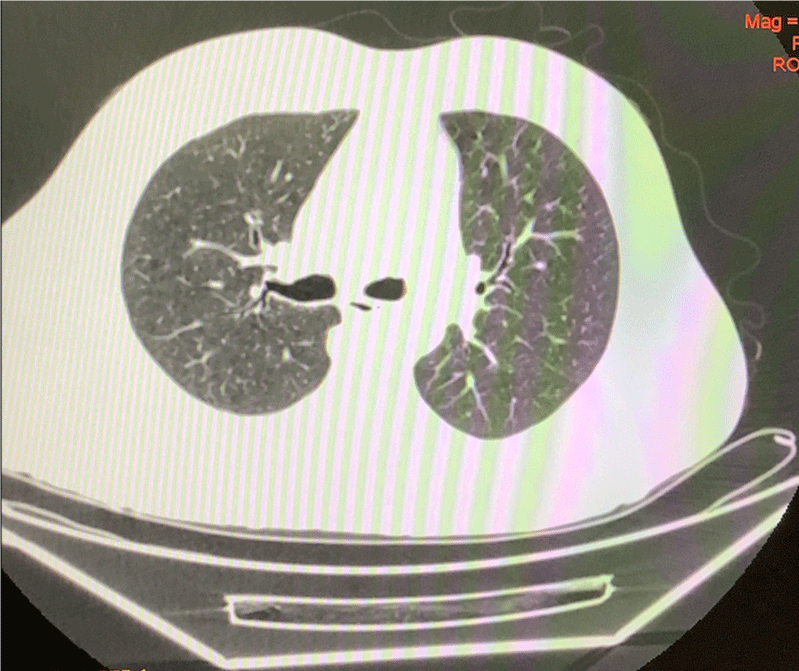

Our data of 150 pre-operative Oral Cavity Squamous Cell Carcinoma patients from 15th April to 31st July was analyzed. The patients were admitted 2 days before the date of surgery for initial assessment by RT-PCR testing. The patients with a negative RT PCR report were then subjected to HRCT Thorax and only if there were no signs suggestive of a COVID-19 infection on the HRCT scan as well, the patients were taken up for surgery. Based on the CT findings, the level of suspicion of COVID-19 infection was graded using CO-RADS classification (Table 1) (Figures 2,3). The detection rate of COVID-19 infection based on the initial RT-PCR and HRCT Thorax was compared (Figure 1). The purpose of study was explained and informed consent has been taken from patient. The ethical clearance was obtained from ethical subcommittee of institute before commencement of study.

Figure 3: HRCT Thorax (CO-RADS 2): Left apical segment nodular opacity 12.7 x 11.4 mm.